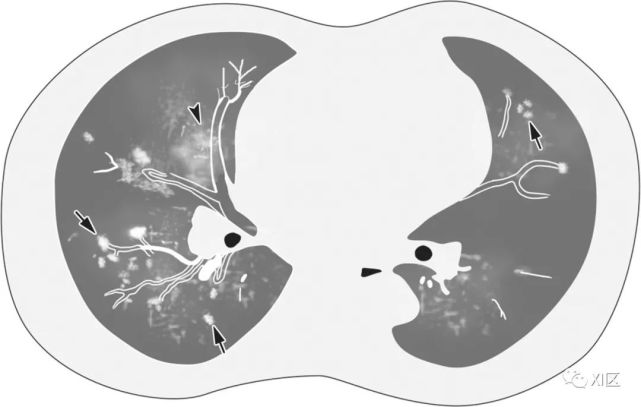

图片

图23 27岁男性,出现咳嗽和咳痰,诊断为MERS冠状病毒引起的肺炎。(上)最初的胸片显示,在下肺的两个区域,特别是在左心后区域,结节影(箭)区域增加。同一天在右下肺静脉水平(中上)以及右心房和下腔静脉交界处(中下)的冠状位重建图像(3mm) 椎体水平的图像(下)显示了两下肺叶的多发斑块状和结节样实变和GGO(箭头)。